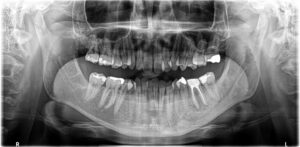

術後約6か月:だいぶ黒い影が小さくなり、骨ができてきました。

根尖病変は治癒傾向にあるため、セラミッククラウンを入れて治療終了となりました。